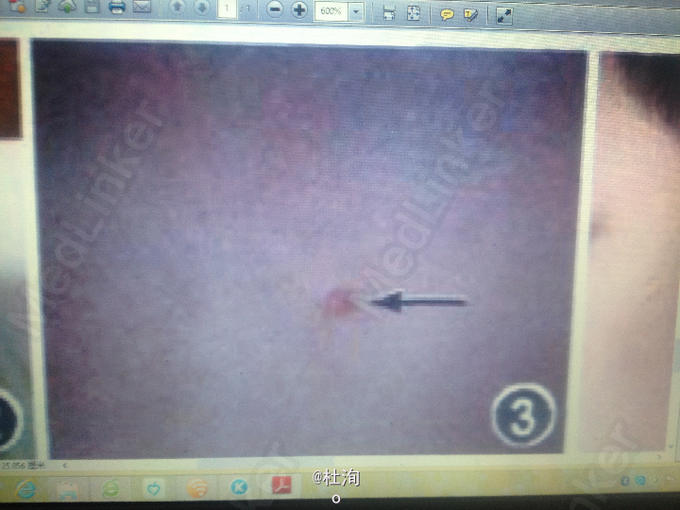

男性,12岁。自出生即发现颈部右侧瘘管及双侧耳前瘘管,语言发育迟缓。患者母亲为聋哑人,有双侧耳前瘘管,并有双侧鳃裂瘘管手术史。纯音测听结果示:双耳全聋;耳部CT示:双侧前庭导水管扩大。肾脏B超检查未见异常。患者的舅舅有双侧耳前瘘管及双侧鳃裂瘘管手术史。无听力损伤表现。肾脏B超检查结果示:右侧肾缺如。患者的外婆,聋哑人,有双侧鳃裂瘘管及双侧耳前瘘管。未能配合行进一步检查。

查体见:瘘管处挤压见清亮液体流出,患者的纯音测听检查结果:双耳中重度感觉神经性耳聋;耳部CT示:双侧前庭导水管扩大

诊断:鳃一耳-肾综合征 处理:建议行瘘管造影检查,明确瘘管所经位置,制定手术方案切除瘘管。